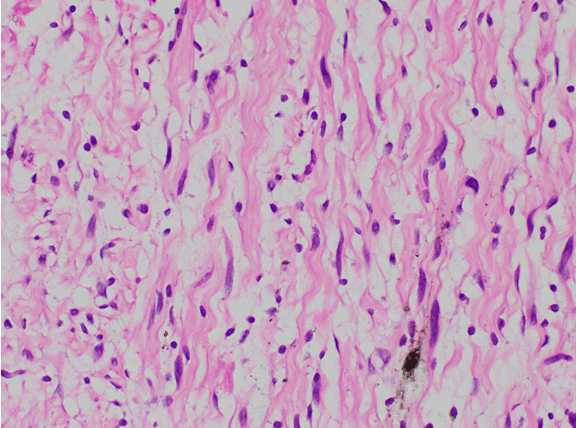

The gross pathology showed a greyish homogenous cut surface of a 55x50 mm tumor. Pathological examination confirmed the diagnosis of neurofibroma of the vagus nerve. Microscopy showed loosely arranged spindle cells containing slender wavy nuclei with pointed edges. Scattered cells showed enlarged hyperchromatic nuclei resembling degeneration. Mitoses were not increased (Figure 3).

Figure 3: Loosely arranged spindle cells.